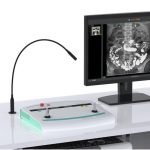

9) Illumination brightness: >=200Lux